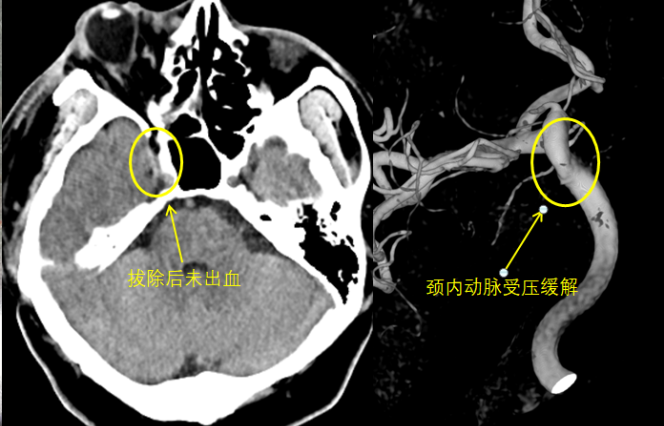

术中立即再次复查脑血管造影和CT,未见颈内动脉出血,动脉的压痕也变浅了。益于神经外科团队丰富的经验及复合手术室的先进条件,患者避免了复杂而痛苦的开颅手术。

术后复查未见颈动脉出血,压痕变浅

术后医生对患者加强了抗炎治疗,患者未出现明显的感染迹象,术后1周复查CTA也未见假性动脉瘤。